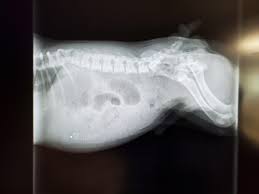

They look like tiny bodybuilders, but their spines are actually made of glass. French Bulldogs carry the exact chondrodystrophic genetic mutation that causes premature spinal degeneration. Their spinal discs turn brittle and calcify before they even reach two years of age.

This makes them highly susceptible to Intervertebral Disc Disease (IVDD), where a disc ruptures and permanently paralyzes their hind legs. You must stop your Frenchie from jumping on and off furniture immediately. Invest in high-traction pet stairs and strictly use a Y-shaped chest harness instead of a neck collar.